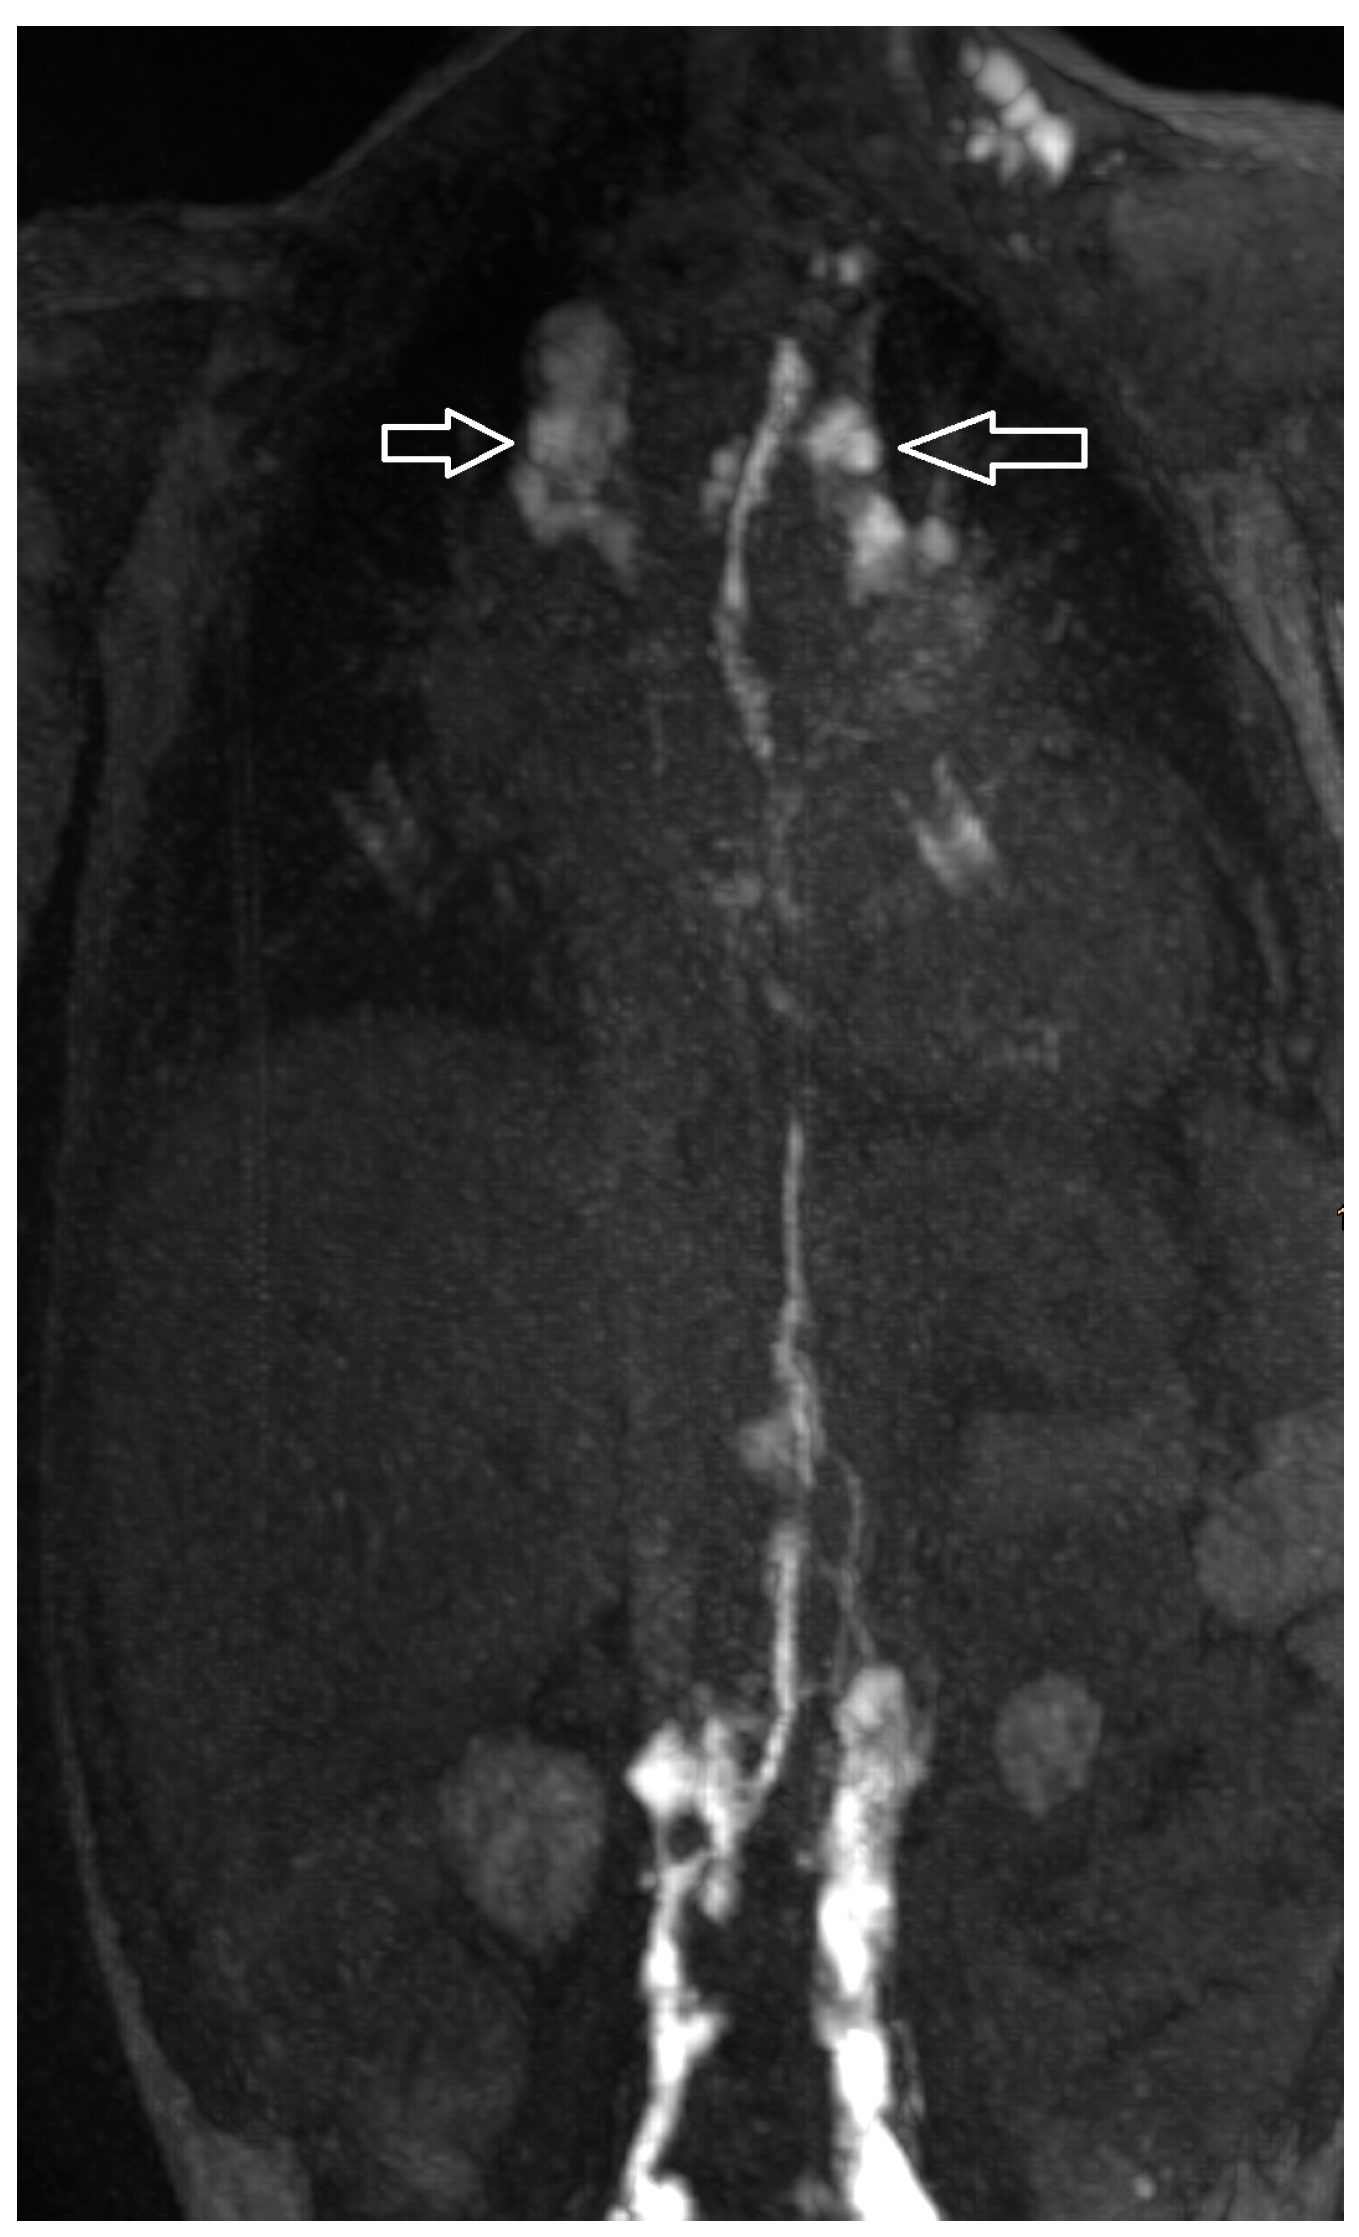

Figure 1.

Intercostal lymphatic flow (a, arrows point at it) and dermal backflow (b, * shows dermal backflow, # is the dilated lymphatic network, arrows point to a doubled thoracic duct with pulmonary effusions, + shows dermal effusions).

Increased signal of lymphatic structures on T2-weighted imaging was considered as abnormal lymphatics. Abnormal lymphatic flow was defined as contrast agent passing from the injection site to any anatomical structure not typically involved in centripetal lymphatic flow to the left venous angle, as previously described by David Biko. Based on the same publication, we described dermal backflow (Figure 1a) and intercostal lymphatic flow (Figure 1b) when intranodal contrast passed retrograde into the intercostal space along the chest wall or into the subcutaneous tissue [13].